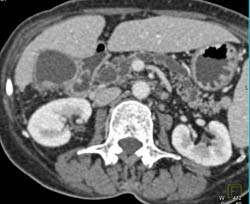

Diagnosis

Ampullary Mass